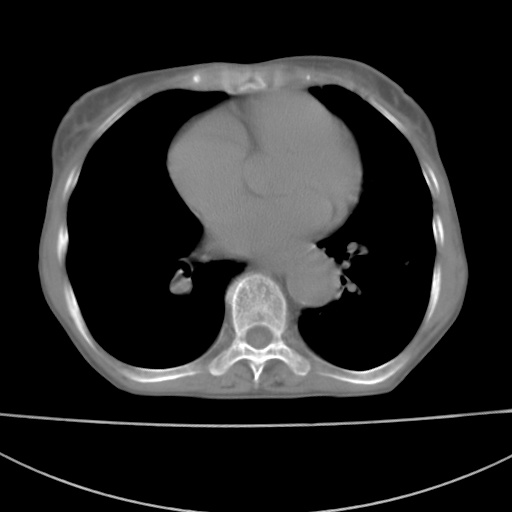

患者 女 67岁,反复咳嗽咳痰2年,加重伴喘及双下肢浮肿1月

诸大血管及f肺门血管增粗迂曲.左下肺多发薄壁空腔影.部分非也透亮度增高.薄曾扫描可区分肺气肿类型.考虑1.慢性支气管炎 2.左下肺支气管扩张 3.肺气肿 4 肺动脉高压5.是否有先心病病史

考虑1.慢性支气管炎 2.左下肺支气管扩张 3.肺气肿 4 肺动脉高压

慢支炎、肺气肿、双肺感染、左下囊状支扩。

慢支、肺气肿、肺动脉高压;左下肺囊状支扩并粘液栓形成。